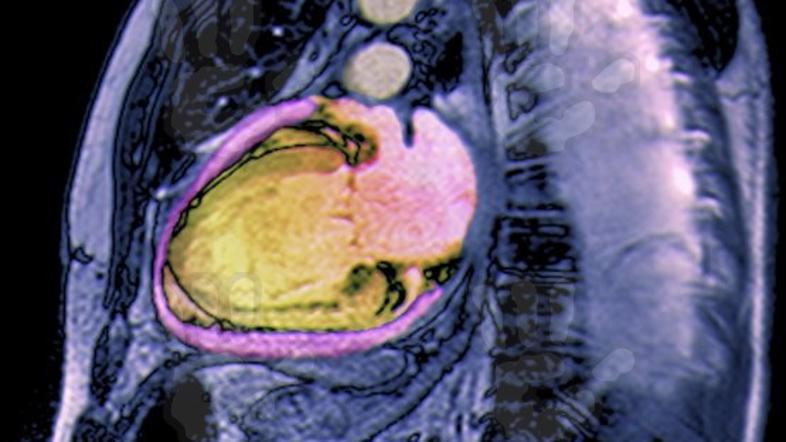

Srčno popuščanje: Bolezen z veliko trpljenja in težkim koncem

Vzrok za dva- do trikrat več smrti kot napredovani rak dojke in rak črevesja, saj preživi manj kot polovica bolnikov,

Srčno popuščanje ne vpliva le na kakovost življenja, lahko torej pripelje do težkih zapletov, celo do odpovedi srca. Nasploh je smrtnost še vedno zelo visoka, pet let po odkritju srčnega popuščanja preživi manj kot polovica bolnikov, je opozoril Dr. Cevc.

Kronično srčno popuščanje je bolezensko stanje, pri katerem okvarjeno srce ne zmore črpati dovolj krvi za potrebe drugih organov. Do srčnega popuščanja lahko pride zaradi poškodbe srčne mišice, ki jo lahko povzročijo povišan krvni tlak, bolezni srčnih zaklopk, srčni infarkt, vnetje srčne mišice ali druge bolezni srčne mišice: "Ko zdravnik predpiše zdravila, jih mora bolnik jemati redno in natančno po zdravnikovih navodilih. Zdravljenje je namreč največkrat sestavljeno in prilagojeno za vsakega posameznika," je dodal prof. dr. Bojan Vrtovec, vodja oddelka za napredovalo srčno popuščanje in transplantacije srca v ljubljanskem Univerzitetnem kliničnem centru.